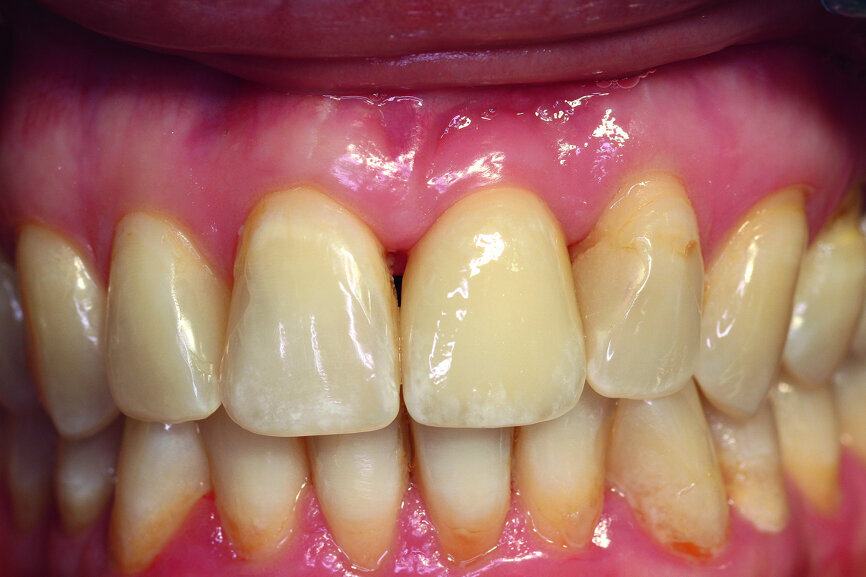

A 40-year-old female patient presented to our dental surgery with an irreparable tooth #21 (Fig. 1). The periapical radiograph revealed an approximately 7 mm periapical translucency with widening of the periodontal ligament in the upper third of the root (Fig. 2). Owing to the clinical conditions (high smile line and good oral hygiene), we decided to use a two-piece ceramic implant, ZERAMEX XT (Dentalpoint).

Fig. 1: Initial clinical situation.